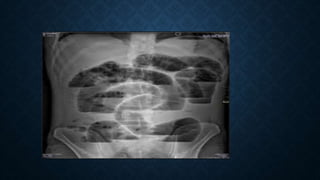

This document provides an overview of x-rays for medical students, covering topics such as ensuring x-rays are well-aligned, exposure levels, common artifacts and anatomical features, abdominal x-ray positions and views, and specialized x-rays including barium swallows, enemas, and tests to examine the esophagus, small bowel, biliary tree, and kidneys.